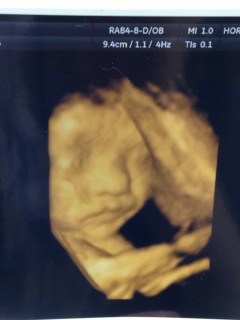

第二子の男の子です。 体重は1,776gで順調です。鼻が高そうで、この鼻は完全に夫の鼻です(^^) 3歳の上の子も一緒にエコー見て、これが赤ちゃんのおちんちんだよと説明されるとニヤけていました。 このまま順調に育ってね~。